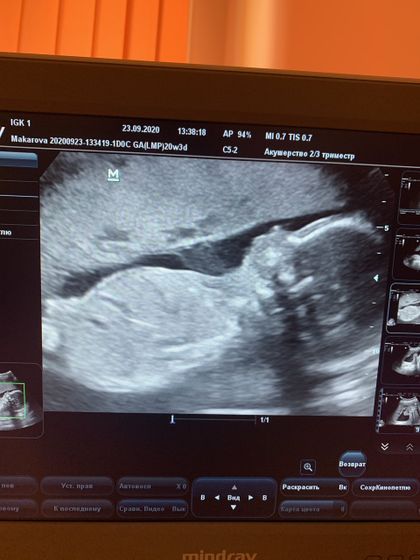

У нас всё хорошо! Вес 373 грамма, акушерский срок 20,3, соответствует размерам 20,5. Шейка уменьшилась с 41 до 36, но тоже вроде нормально.Конечно, бесплатное узи очень отличается от платного, врач молчаливая и неприветливая, даже пол не сказала. Но великодушно разрешила сделать фото с монитора ?? И мне повезло, что пол тут так хорошо виден ? Эксперты, кого видим?

Мальчишка)))

Девочка)